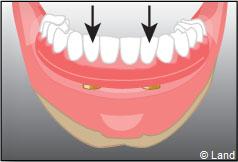

Exemple d’une réhabilitation complète implantaire

Situation clinique initiale

Situation clinique terminée